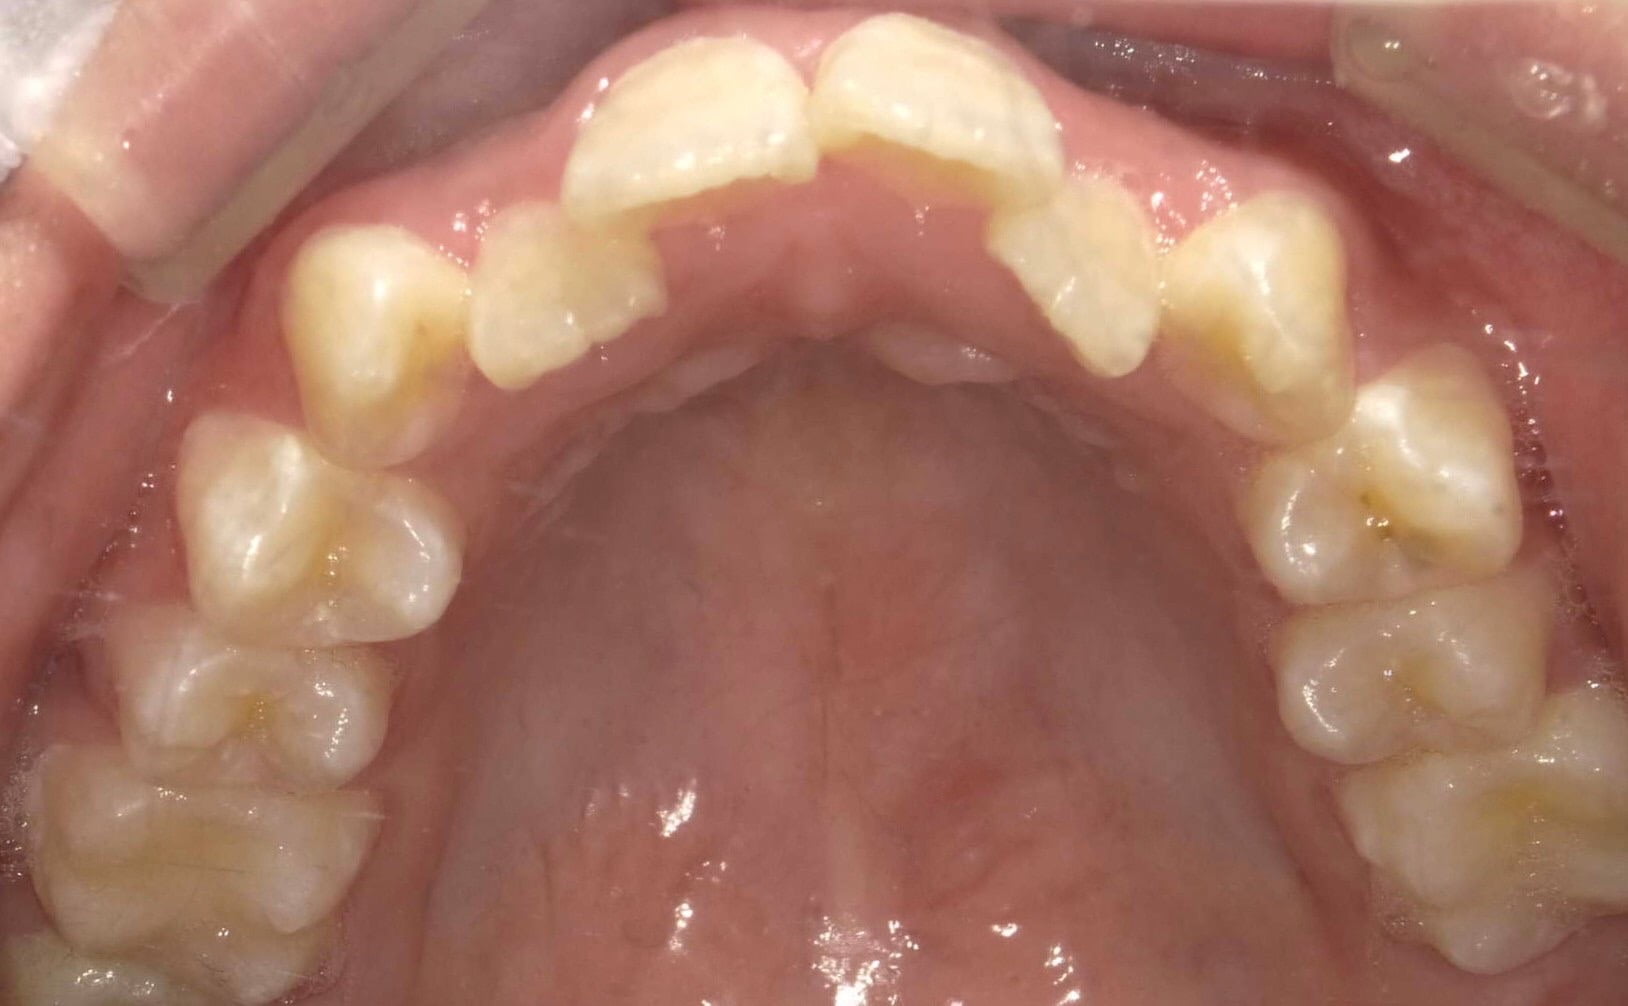

• お悩み

左にずれている

将来入れ歯になりたくないため予防

年齢

52歳/女性

治療期間

2年

施術説明

歯並びや噛み合わせの不全をアライナー型矯正装置を装着し、歯並びや噛み合わせを改善し適切な状態にする治療です。

副作用

装着したまま糖分の入った飲料を取ると、虫歯を発症しやすくなります。正しい装着方法で1日20時間以上使用しないと、目標とする治療結果を得れないことがあるため、きちんとした自己管理が必要になります。

将来入れ歯になりたくない

ため予防